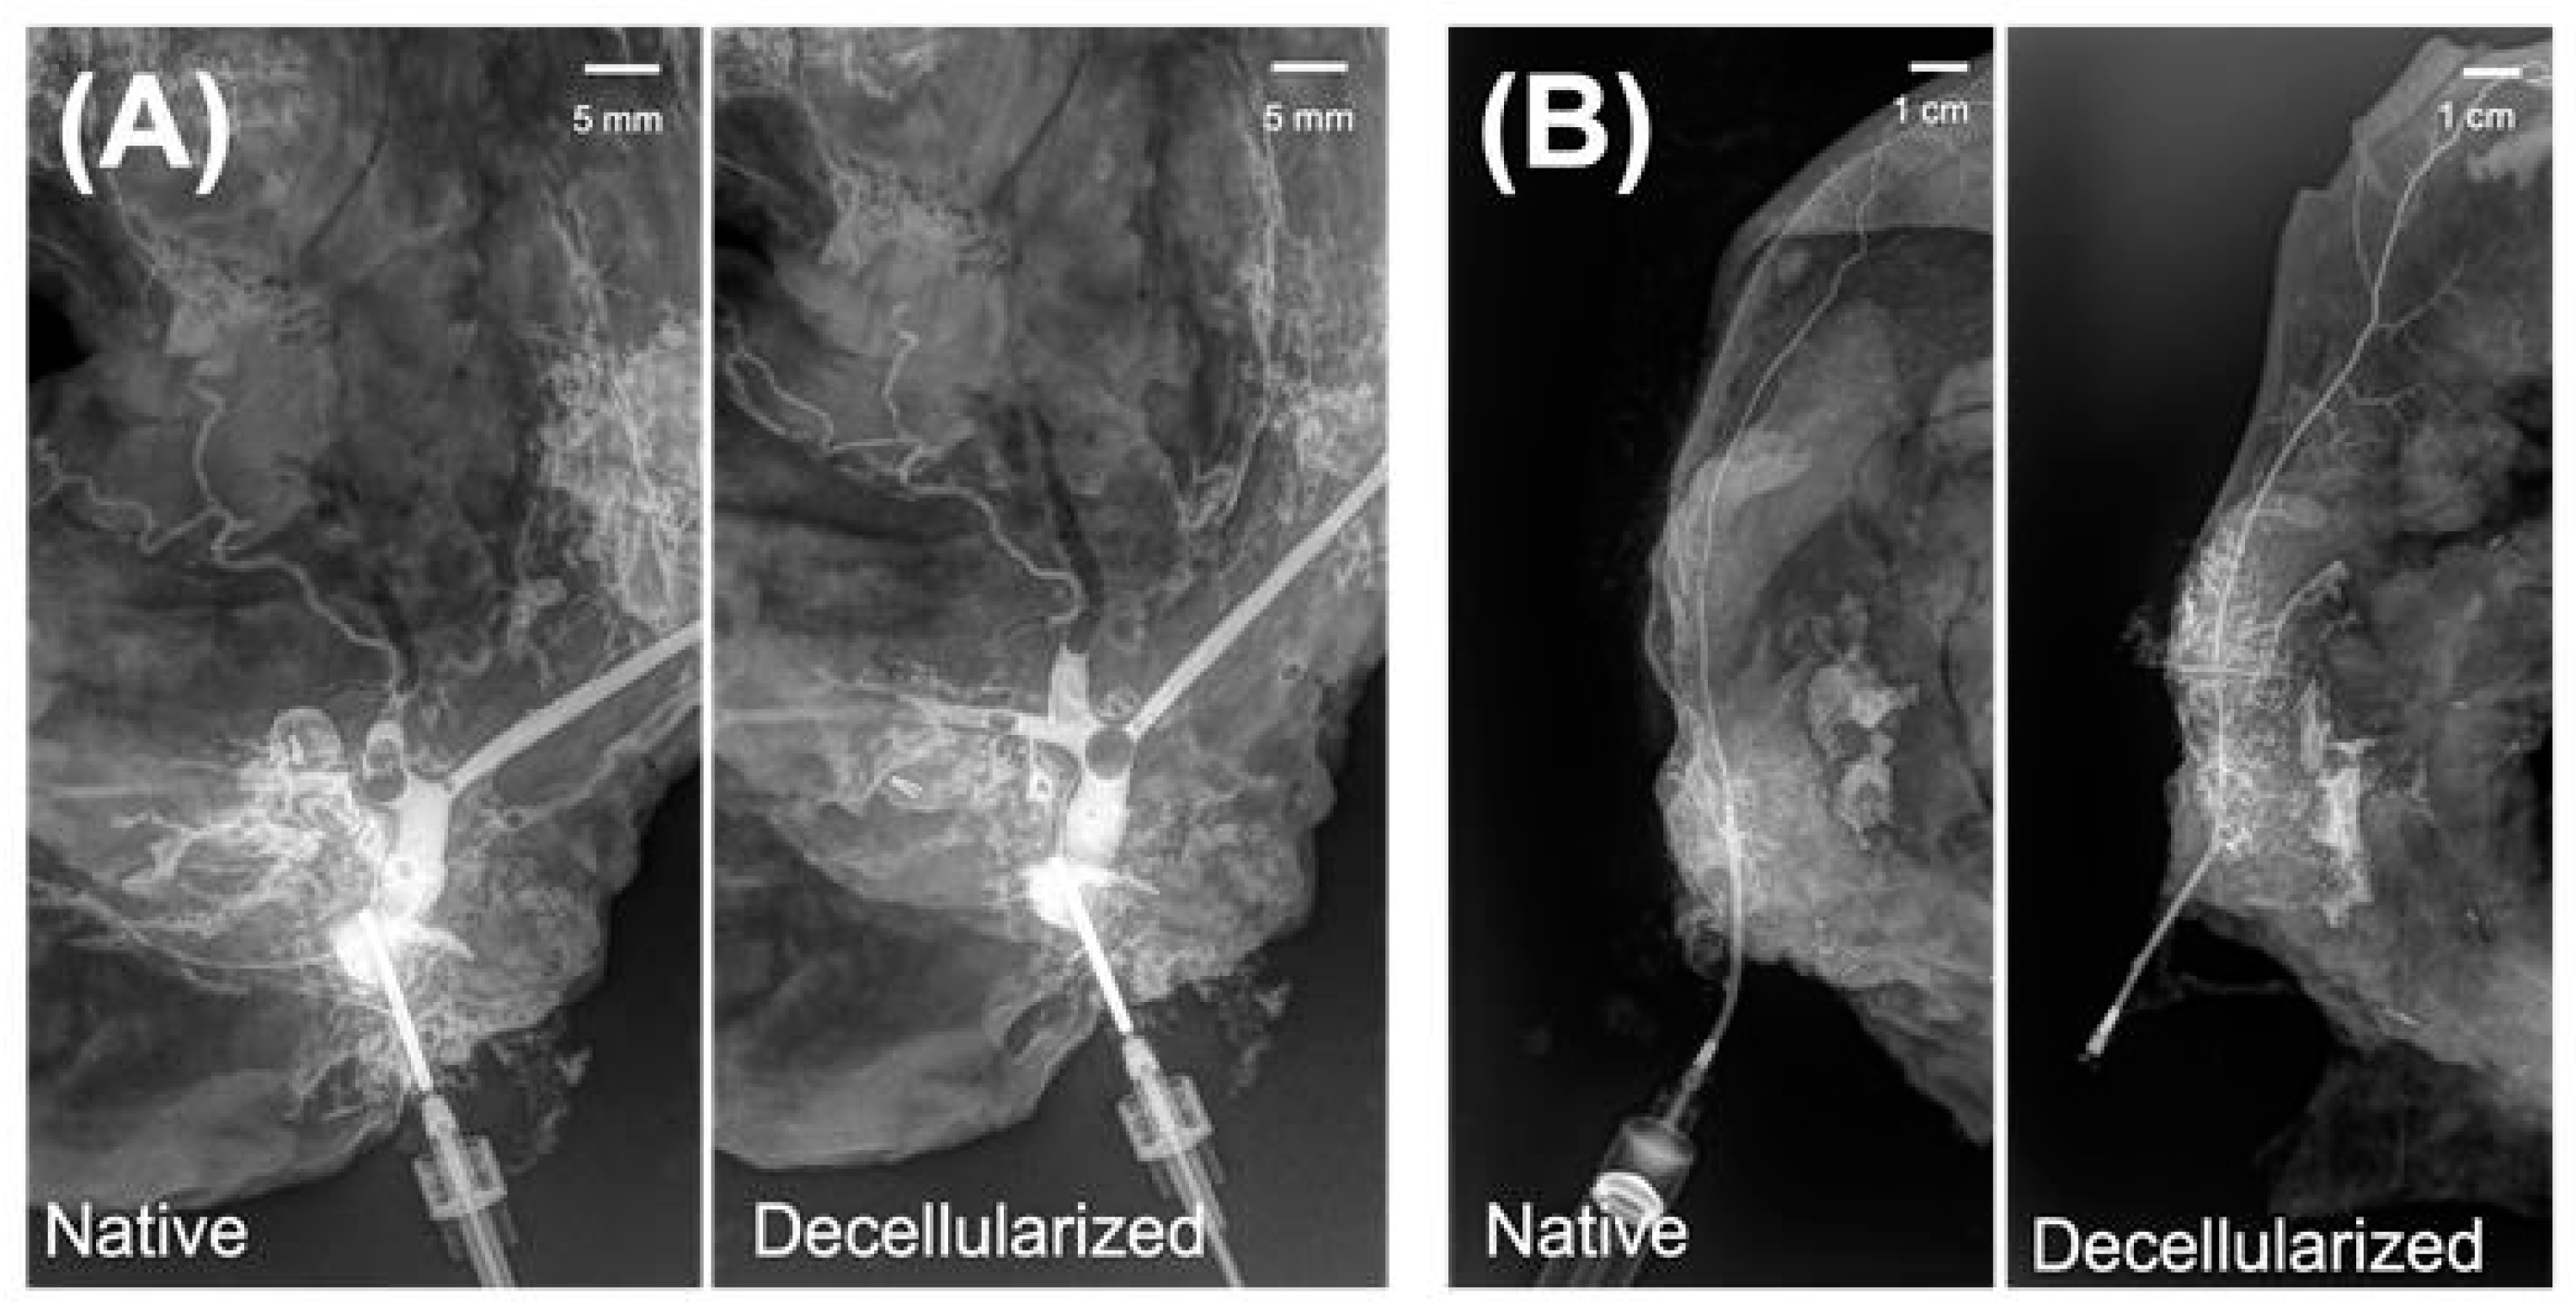

3.3. Microarchitectural and Mechanical Characteristics of Decellularized Facial Grafts